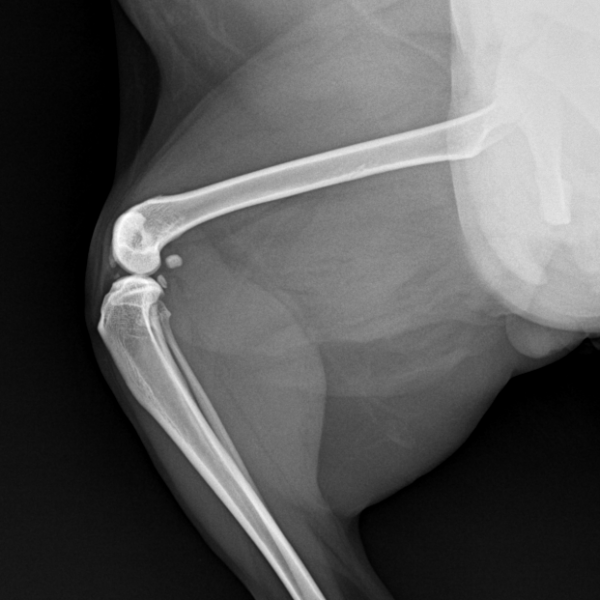

9세 뱅갈 고양이 슬개골 탈구 케이스

고양이 슬개골탈구 수술 case

방사선 촬영 시 올바른 자세로 촬영하면

탈구된 슬개골이 일시적으로 제자리로 돌아가

정상처럼 보일 수 있습니다.